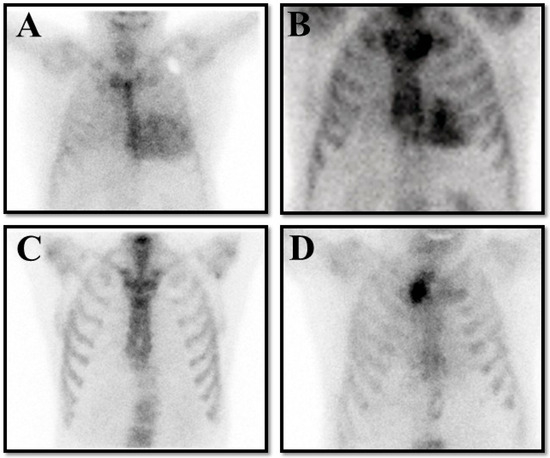

- Cardiac Imaging: The expanding role of advanced imaging modalities—including echocardiography, cardiac magnetic resonance, computed tomography and nucear imaging—in the early detection and accurate phenotyping of cardiomyopathies.

- nuclear imaging